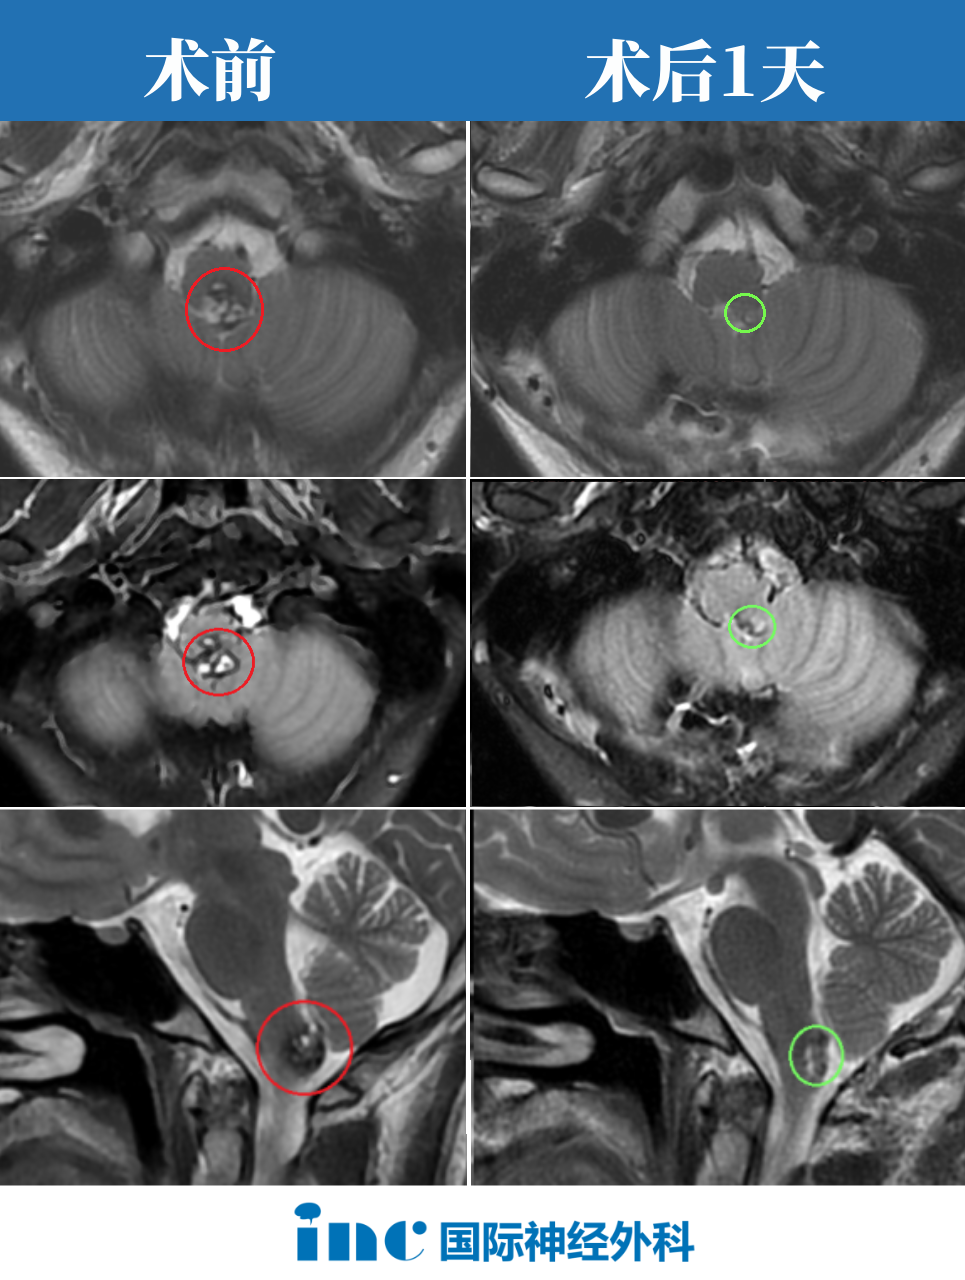

术前情况:20岁大学生,意识紊乱并逐渐恶化,左侧偏瘫,MRI显示脑干中脑出血,急性梗阻性脑积水。病变位于脑干腹侧中脑中线,体积10.7立方毫米,深度42.5毫米,肿瘤侧倾角11.6°(图A、B)。

手术入路:巴特朗菲教授根据患者病情、肿瘤生长及MRI影像特征,先行脑室引流术,随后采用双额骨瓣开颅、经基底纵裂入路完成病变全切。

术后情况:Maritta术后恢复顺利。意识和偏瘫症状迅速改善,脑积水消退。患者步行出院,3个月后随访无任何神经或认知功能障碍。术后MRI显示轴内血肿和血管病变完全切除(图C、D)。

图A、B显示术前MRI影像,确诊出血性中脑海绵状血管瘤。黄色虚线标示肿瘤深度(42.5毫米)。图C、D显示血管病变完全切除后的术后MRI,病灶全切,压迫占位效应解除,脑组织复位,未见手术损伤如脑出血或脑水肿。